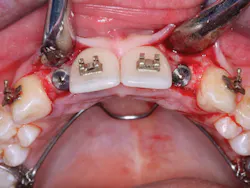

2. In the facial-lingual orientation, locate the osteotomies in the center of the ridge and parallel with the adjacent teeth. Use finger contact on the facial and lingual of the ridge while making the drill cuts. If you feel extra vibration on one or the other side of the ridge, reorient the drill appropriately (figures 4-7).

Figures 4-7: This series of images shows a clinical situation, the cone beam images, and the freehand implant placement.